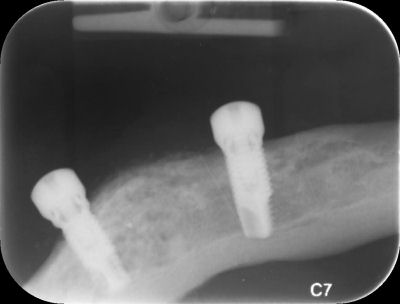

When implants are used to secure a denture to your jaw bone, they are called 'implant overdentures'. This name has been used because the denture sits on top of the implants. Implant overdentures can help people with severe jaw-bone loss to have a secure denture wearing experience. The procedure involves placing two or three implants usually into the lower jaw bone. Once the implants integrate into the bone, a denture is then made to fit over the top of the implants.

Small clips are used to join the implants to the dentures. The implant overdenture can still be removed from your mouth like a normal set of dentures to be cleaned and to give your gums a rest at night. The biggest difference is that they hold much better to your lower jaw compared with a conventional set of complete dentures. This will give you more confidence that your dentures will remain secure when eating and speaking.

Implants are fixed to your jaw bone and do not move. For people that have lost all their teeth, their jaw bone may shrink over time, making it increasingly difficult to function comfortably with complete dentures. Removable dentures are not permanently fixed in place, they can move around when you eat and speak. Implant overdentures can help to stabilise an upper or lower denture by using clips that attach to the implants that are anchored in your jaw bone. Implant overdentures can initially be more cost effective than fixed implant bridges (fixed bridges on four or more implants).